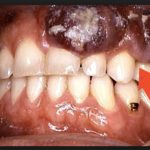

Каждому человеку важно знать, как на любом этапе выглядит рак десны и как проявляется – это поможет вовремя насторожиться и проконсультироваться с врачом. Опухоль замечают не сразу, потому что небольшое уплотнение не ощущается, а эстетически оно малозаметно, и человек не придает ему значения. Когда заболевание прогрессирует, образование быстро разрастается, сопровождаясь определенными признаками. Когда у человека рак десны, начальная стадия, симптомы включают в себя появление на тканях белесых или багровых пятен. Также наблюдается:

- Отеки – в месте поражения возникают припухлости. Иллюстрируют, как выглядит в таком случае рак десны, фото в интернете на сайте клиник, которые занимаются лечением онкологических недугов.

Обычно на первые признаки рака десны указывают язвы – множественные или одиночные, которые находятся в районе локализации опухоли. У язв правильная форма и четкие границы. Одновременно пациент начинает чувствовать, что стал больше уставать, ему сложнее засыпать по вечерам. По мере того, как развивается рак десны, жжение становится сильным и уже не купируется обезболивающими средствами. Повышается температура, которая не сбивается лекарствами и указывает на воспаление в организме. К сожалению, пациент обращает внимание на это, когда рак уже интенсивно развивается.

Рак нижней десны можно определить по локализации боли. Пациент чувствует сильный дискомфорт при глотании и жалуется на неприятные ощущения в области языка, шеи, челюсти. Болезнь может продолжить развиваться на отдельном участке или распространиться по всей ротовой полости. Если болевые ощущения отдают в уши, виски, лоб, вызывают мигрень, чаще всего диагностируют рак верхней десны. В обоих случаях возникают проблемы с чисткой зубов из-за боли и постоянного выделения крови, которую на заключительных стадиях трудно остановить. Язвы могут нарывать, вызывая заражение здоровых участков.